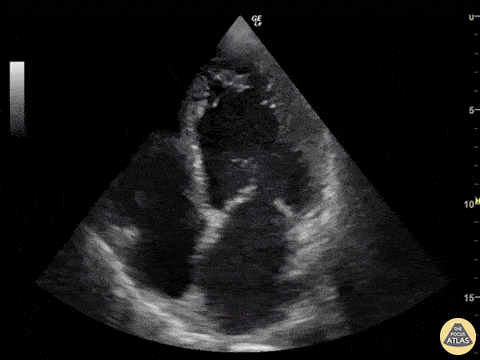

A 50-year-old male presented to the ED with signs/symptoms of acute ischemic cerebrovascular accident (hemiplegia and dyslalia). Head CT confirmed the presence of a subacute ischemic event. Bedside POCUS (apical four chamber view) revealed severe LV global hypokinesis and the presence of an apical thrombus; the likely etiology of his cardioembolic event. Renato Temabli, EM Physician Brazil @JediPocus